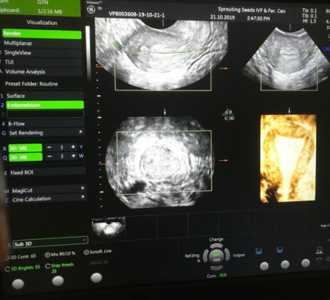

Ultrasonography in Infertility

Ultrasonography forms a key tool in monitoring patients with infertility. It mainly helps in monitoring the growth of the follicle (Egg in the ovary), its rupture and also to monitor the response of the endometrial lining in response to the egg growth and subsequently its release from the ovary. This basic procedure is done by transvaginal sonography(TVS), is a non invasive and cost effective method of determining ovulation. This facility in available at all fertility clinics and at certain sonography institutes and clinics and is called follicular study.

Follicular Study

Two main things that are monitored in a follicular study are the ovaries and endometrium. It is ideally started on the second or the third day of the periods when the woman is actually menstruating. The antral follicular count (AFC, number of eggs recruited in one particular cycle) is noted. This is an indirect method to detect the egg producing capacity in the woman. The ideal AFC is 3-6 eggs of size less than 10mm size in each ovary. Less means low egg producing capacity commonly seen in women above 30 years of age. More may indicate presence of polycystic ovary.